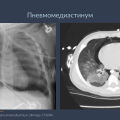

✅ Интерстициальная эмфизема легких (ИЭЛ) — ключевые признаки: ветвящиеся пузырьки вдоль сосудисто-бронхиальных пучков, отличие от воздушных бронхограмм, осложнения (пневмоторакс, пневмомедиастинум).

✅ Пневмоторакс и пневмомедиастинум — как не пропустить напряженный пневмоторакс у новорожденного?